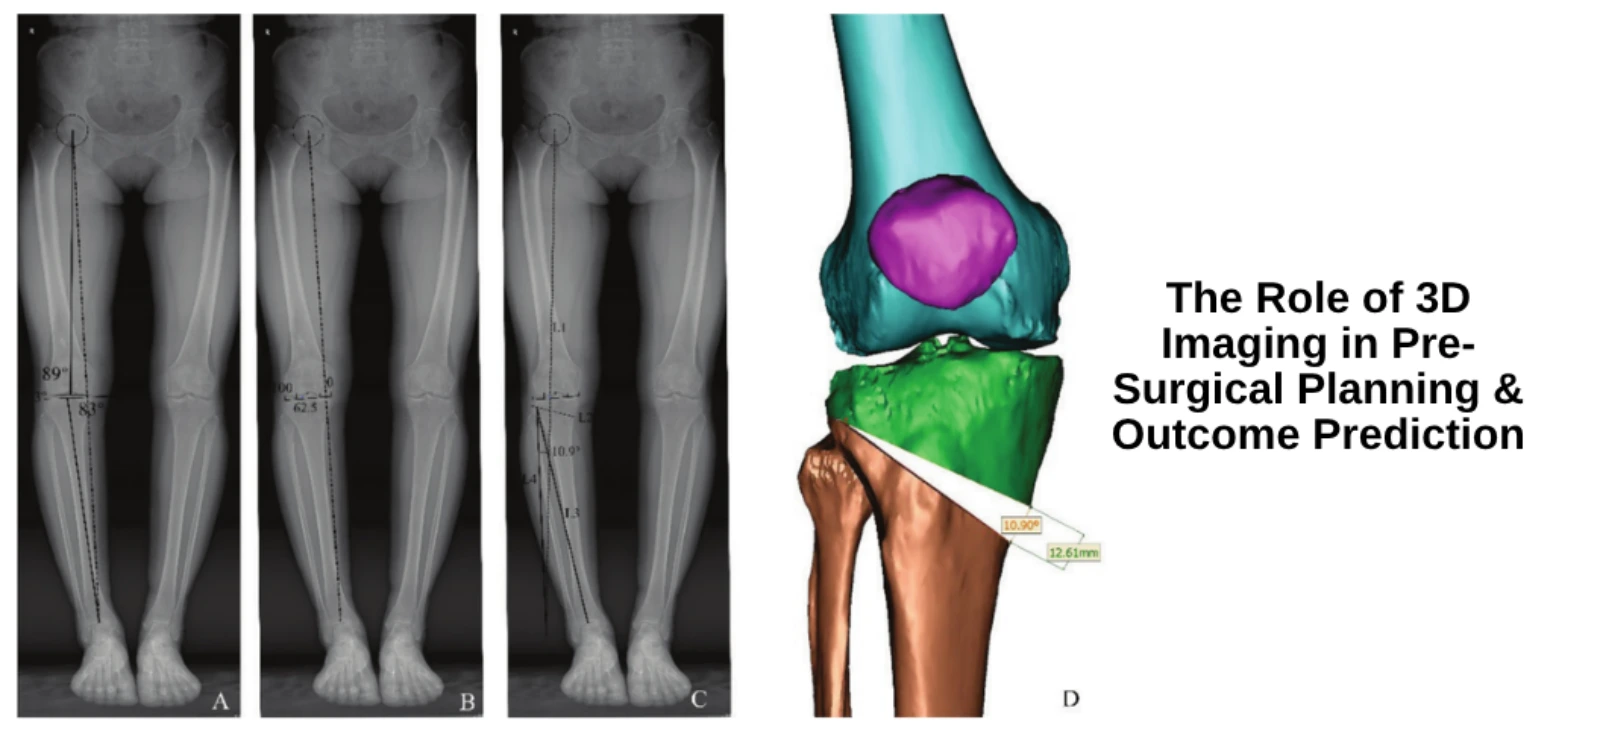

Sports Testing for Injury Prevention: What Bangalore Athletes Need to Know Injuries can derail the training and careers of athletes if not prevented through targeted strategies. Sports testing is emerging